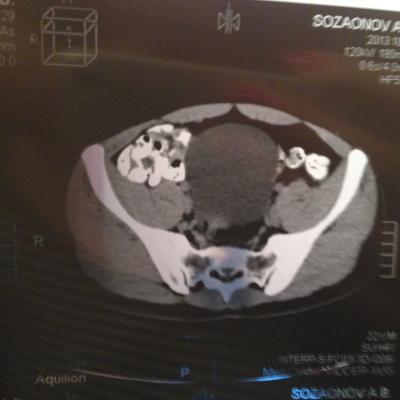

проведена МСКТ области таза!Внеорганных дополнительных патологических образований,лимфаденопатии или свободной жидкости в области таза не выявлено.

Мочевой пузырь-наполнен,стенки не утолщенны,паравезикально-без грубой органки.

Граница между предстательной железой и пузырем несколько четкая,контур пузыря на данном уровне не деформирован.

Предстательная железа-без грубой органики,еденичные микрокальцинаты.

Семенные пузырьки-конфигурация не совсем типична,примерный размер правого 26*28мм.Отмечаются признаки кистовидной трансформации и микрокальцинации обоих пузырьков.Наибольшая из кист слева достигает 9 мм.Обращает на себя внимание неравномерная кальцинация стенок крупных регионарных(текстикулярных)артерий с обоих сторон.

Костно-деструктивных изменений характерных для mts со стороны костей таза не отмечено.

Параректальная клетчатка-не изменена,патологически увеличенных лимфоузлов в параректальном пространстве не отмечено.M.m.levator ani-без особенностей.

Заключение:на момент исследования,КТ-данных за наличие внеорганных дополнительных патологических образований,лимфоденопатии или свободной жидкости в области таза не выявлено.КТ-признаки в пользу проявлений калькулезного везикулита с элементами кистовидной трансформации семенных пузырьков.